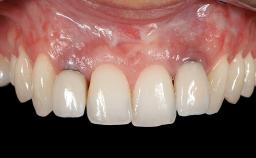

Variations in soft-tissue volume, evidenced either by an overabundance (Evian and coworkers 1993; Levine and McGuire1997; Dolt and Robbins 1997) or by a deficiency of soft or hard tissue can complicate implant-supported rehabilitations in the esthetic zone (Lorenzana 2008; Lorenzana and coworkers 2009). The present case illustrates the replacement of a failing upper left lateral incisor complicated by generalized severe gingival recession in the esthetic zone.